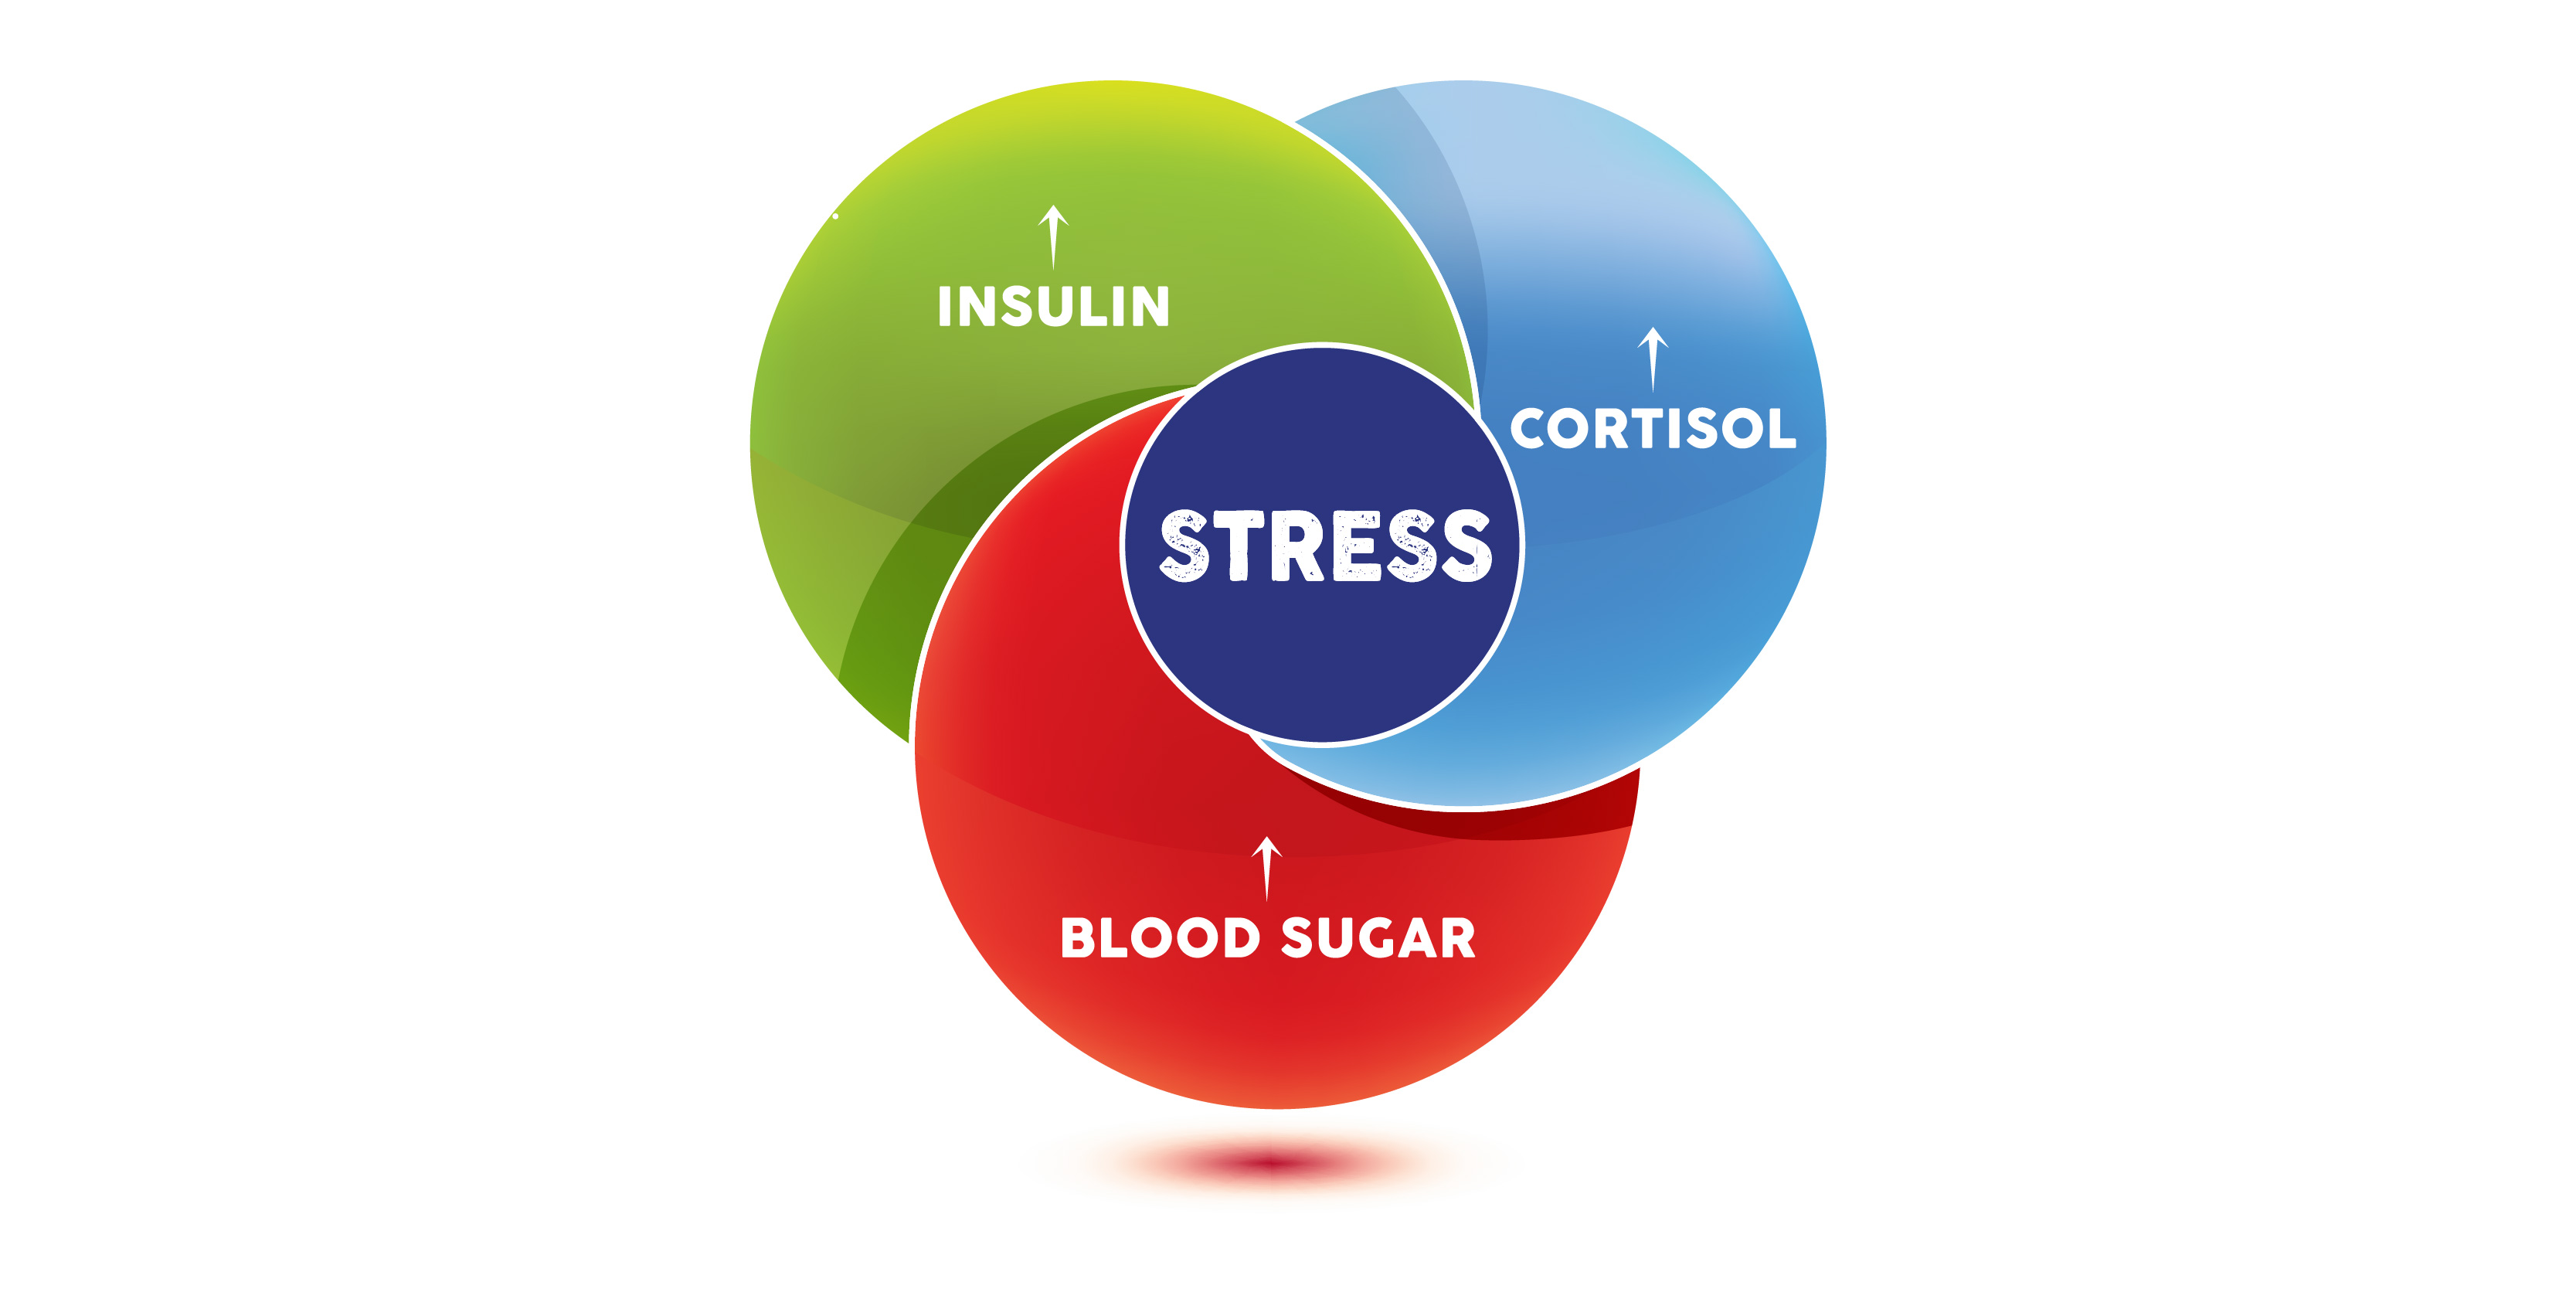

outside of normal physiologic ranges. Conversely, other stressors impacting the body’s regulatory mechanisms through the stress response system, the hypothalamic-pituitary-adrenal (HPA) axis, can lead to blood sugar fluctuation.2,3 Let’s take a closer look at this potential vicious cycle and learn why it’s so important to control blood sugar and the stress response.

The HPA axis does not discriminate by the type of stressor to determine its activation and outcome; it just knows there is stress and it responds. Cortisol is known

as the stress hormone and is released when stress activates the HPA axis. As we now know, cortisol increases blood sugar. If we already have high blood sugar from our meal, our body receives a double-whammy and we end up needing more insulin to manage

it all. As you see, this can lead to that unfortunate vicious cycle we mentioned in the beginning. The more stress we have, the greater chance our blood sugar levels will fluctuate more often and lead to dysregulation over time.